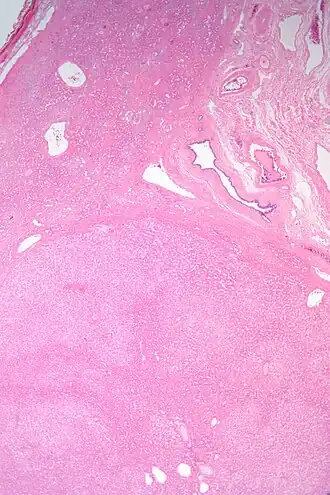

Los adenomas hepáticos son, típicamente, nódulos bien circumscriptos que constan de hojas hepatocitarias con un citoplasma vacuolado de aspecto burbujeante. Los hepatocitos se disponen en un armazón de reticulina regular y más o menos igual a tres células de espesor.

El diagnóstico histológico de los adenomas hepáticos puede ser facilitado por la impregnación argéntica (tinción con sales de plata). En los adenomas hepáticos, el armazón de reticulina y los hepatocitos no forman capas de cuatro o más hepatocitos, como se ve en el carcinoma hepatocelular.

Las células parecen hepatocitos normales y son recorridos por vasos sanguíneos pero carecen de espacios porta y venas centrales.